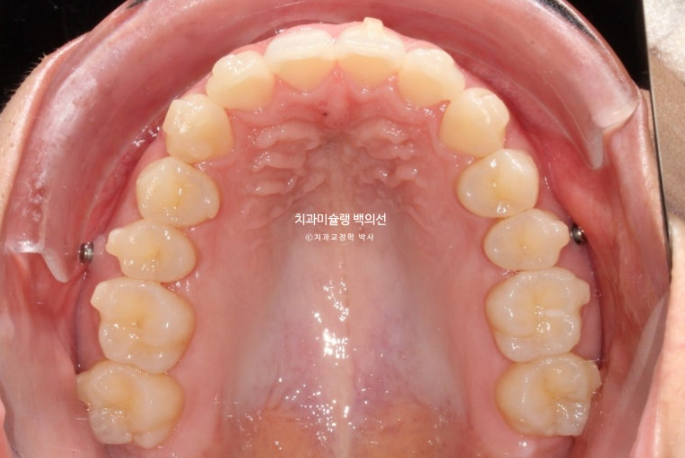

재제작 하는 김에 앞니 뿌리도 치조골 속으로 더 이동시켜서 잇몸건강 측면에서도 안정적인 결과를 도모합니다.

또한 아래 앞니 블랙트라이앵글 사이즈도 치간삭제를 통해 줄이기로 합니다.

2년간 치료기간 동안 치근흡수는 없고 치아뿌리 평행도는 좋습니다.

큰어금니가 약 2mm 사랑니 공간으로 잘 이동했습니다.